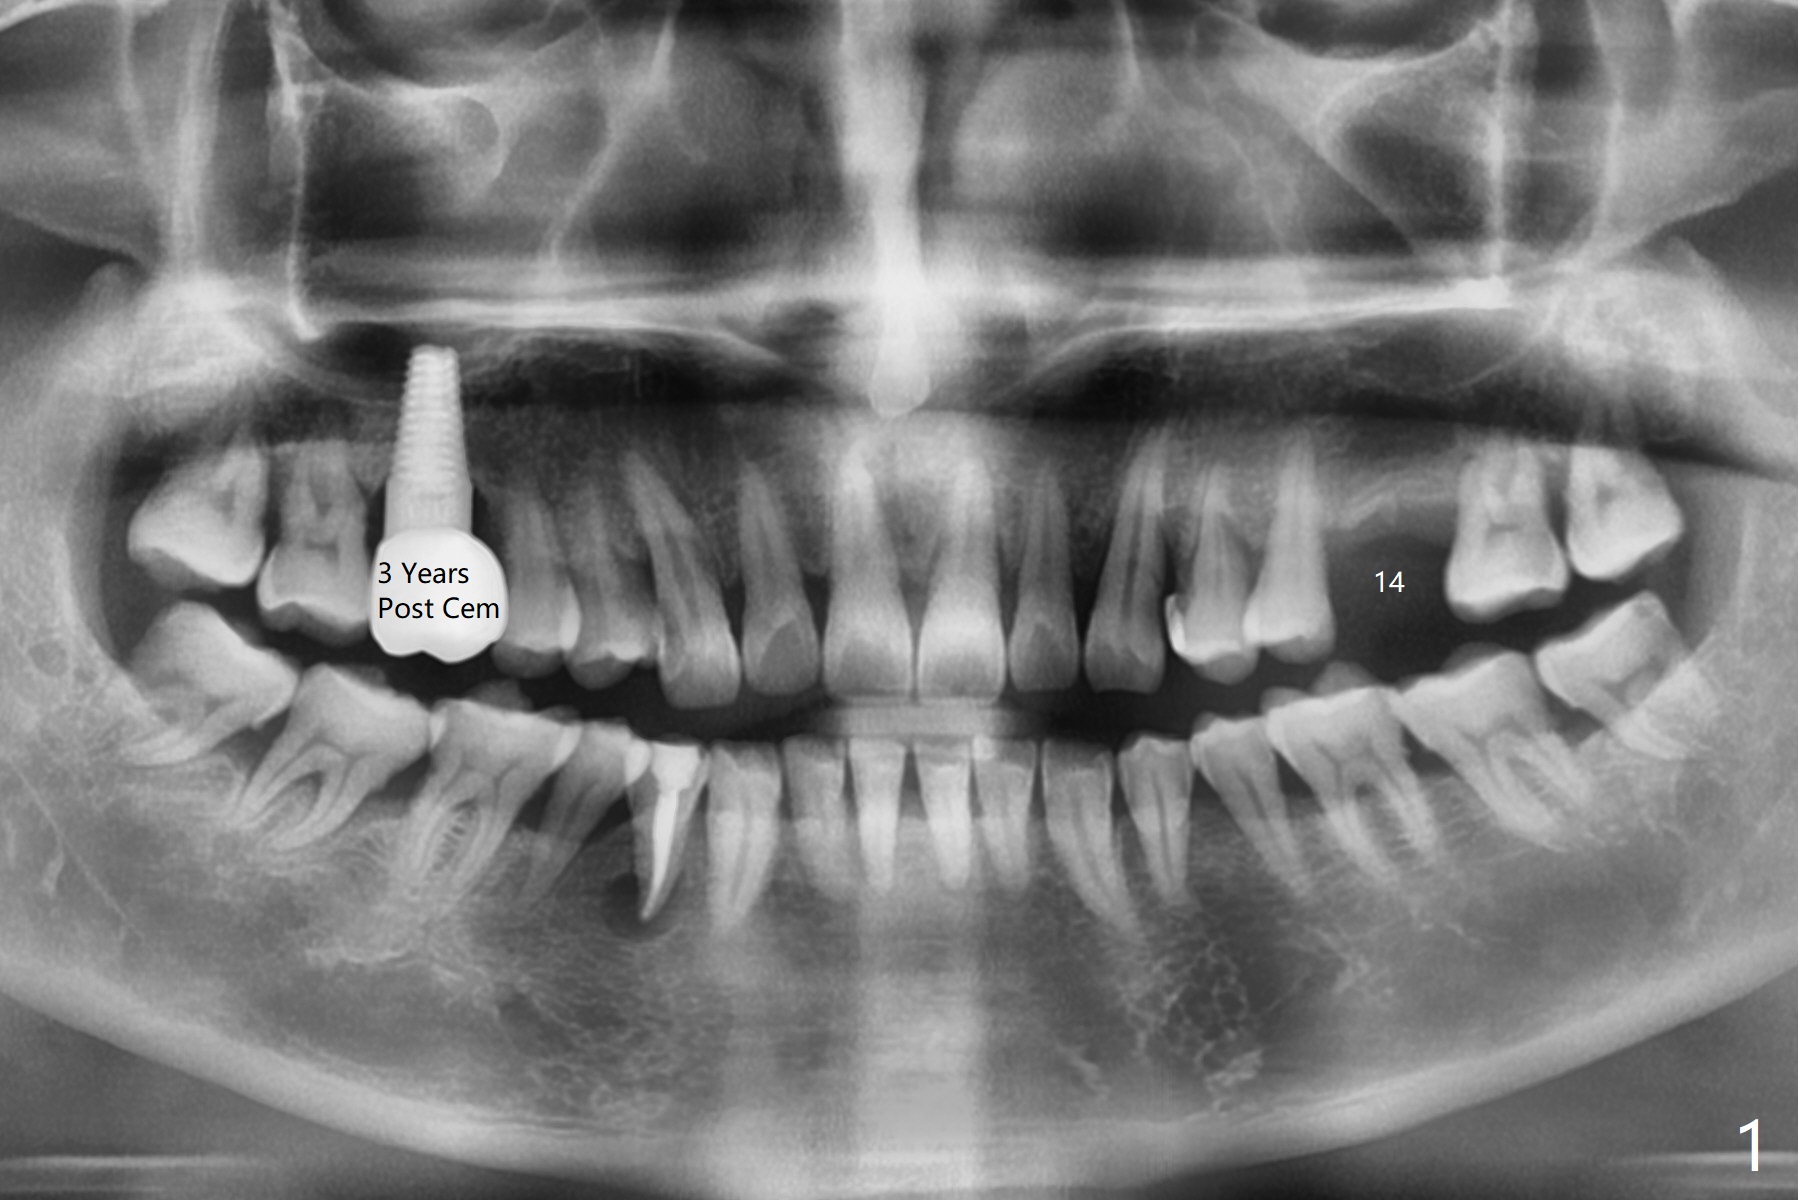

A 48-year-old man with chronic periodontitis wants an implant at #14 (Fig.1). The ridge is narrow. Bone expansion or underdrilling is required (Fig.2). PRF is prepared for sinus lift.